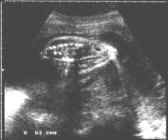

- Coupes transversales :

Ouverture des lames postérieures +/- marquées : Aspects classiquement décrits en U, en V ou en cupule (spina plan) selon le redressement ou la pergence des lames postérieures.

cliché gauche

Visibilité des cloisons dans la hernie méningée confirmant le diagnostic de myélo-méningocèle.